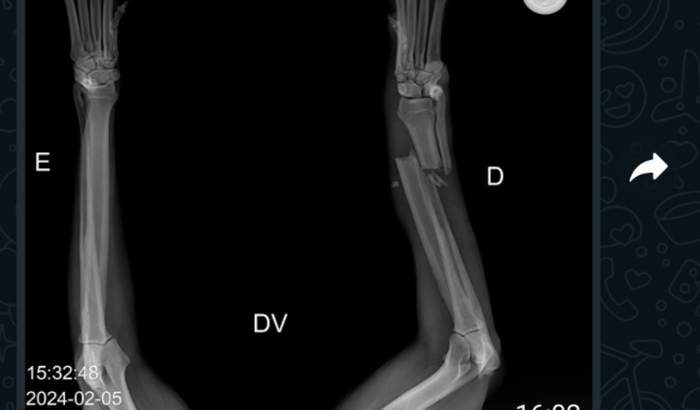

Oi meu nome é Vinicius e estou montando essa vaquinha online para ajudar a Mel. A Mel é uma cachorrinha muito arteira e adora correr atrás dos carros na rua. Infelizmente nessa segunda feira 05/02 a Mel pulou o muro de casa e caiu próxima ao carro que acidentalmente passou por cima de sua patinha, que infelizmente houve uma fratura. Mel ja esta na clinica veterinária medicada e esperando para realizar sua cirurgia. As custas totais estão em torno de 2.200 reais. Por favor ajudem a Mel.